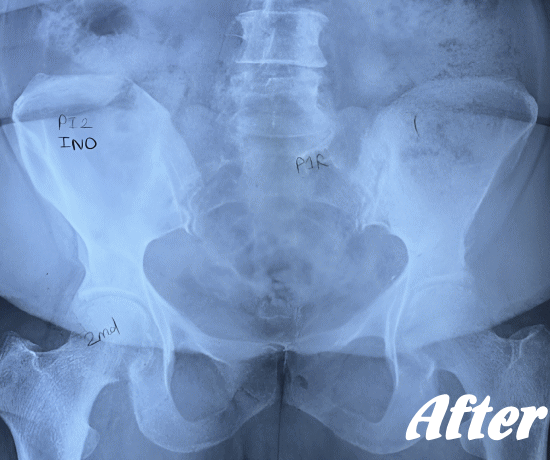

| 施術前 | 施術後 |

HALOカイロプラクティック☆平和島整体院では、梨状筋症候群の場合、多くは骨盤(仙腸関節)や股関節のズレにより、臀部の筋肉が緊張し、坐骨神経を圧迫していると考えます。

したがって、仙腸関節、股関節、腰椎などを本来あるべき正しい位置へと戻すことで、圧迫を取り除き、痛みや痺れの解消を目指します。